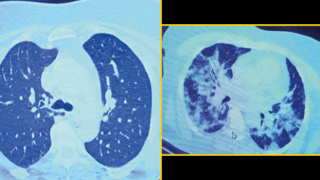

İlaç kullanmayı reddeden koronavirüs hastasının röntgeni ağızları açık bıraktı